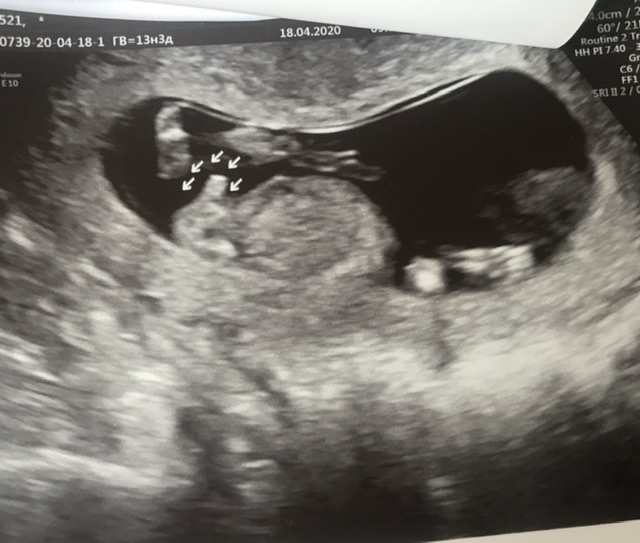

Мальчик?

Срок 13,3. Была сегодня на скрининге, почти не переросли его)) по узи все хорошо, а кровь будет завтра.

Девочки, врач так уверенно сказала «предполагаю мальчика!». Я очень удивилась))) скажите, а вы кого предполагаете по фото?)?